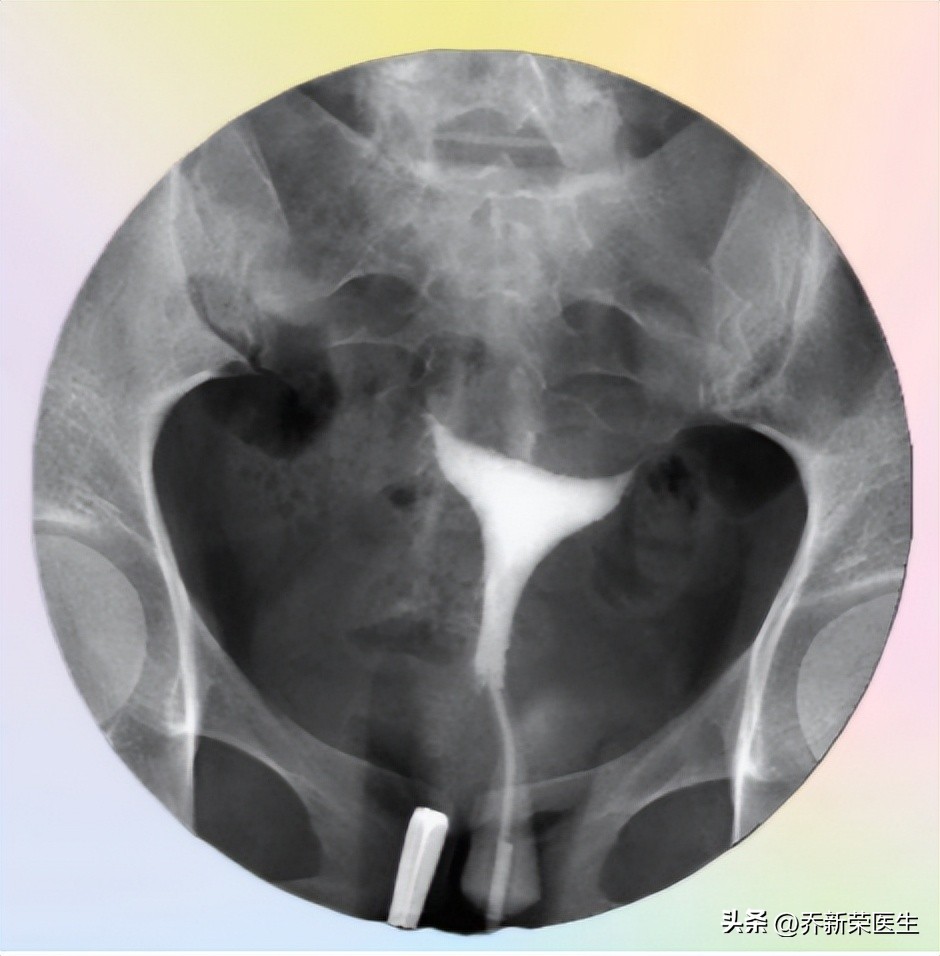

输卵管堵塞是没有办法通过问诊就能显而易见做出诊断的,目前临床常用子宫输卵管影像造影的方式进行检查。

无痛不插管子宫输卵管造影示意图